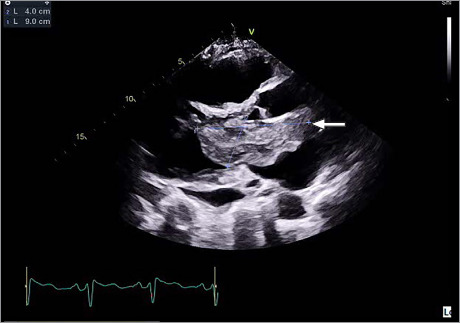

Cardiac myxomas are a rare phenomenon within the general population, and although there are reports of them, giant myxomas are not common in the medical literature. This report presents a case of a giant left atrial cardiac myxoma in a 57-year-old female patient who was largely asymptomatic until she presented with a diffuse thromboembolic stroke. This case report highlights the importance of surgical management of cardiac myxomas and discusses the difference in open vs minimally invasive surgical resection of giant cardiac myxomas.

Abstract Image